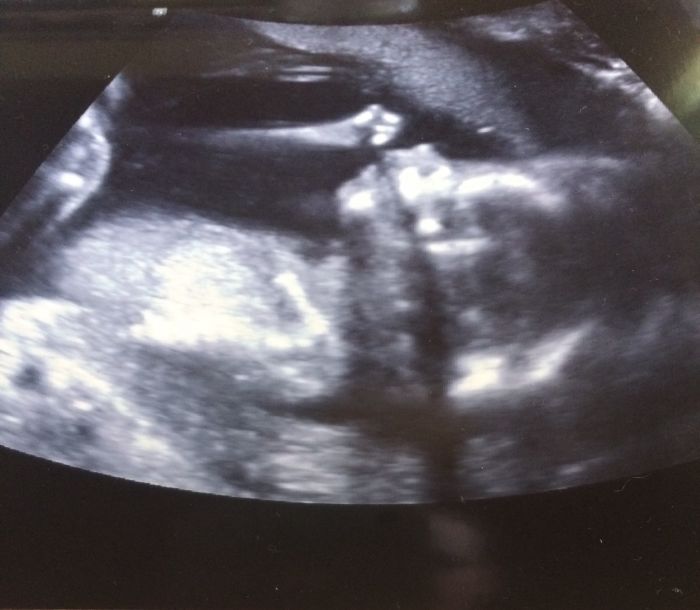

Ahoj holky, tak poradna dopadla moc dobře, tlak ok, moč ok, ta krev kompletně ok, jinak jsem v 18tt a miminko prý vypadá krásně. Jinak mi můj dr potvrdil, že jsem udělala dobře, že jsem ty testy odmítla tak mě to tak vnitřně uklidnilo. Jinak miminko nám ukázalo palec nahoru, dr vtipně poznamenal, že malá vzkazuje, že je to ok:-))...holky a začala jsem cítit regulérní pohyby, nádhera! Jinak mám už domluvený druhý screening:-).

Jo a potvrdili nám tu holčičku tak jsme moc rádi;-)...naše princezna...